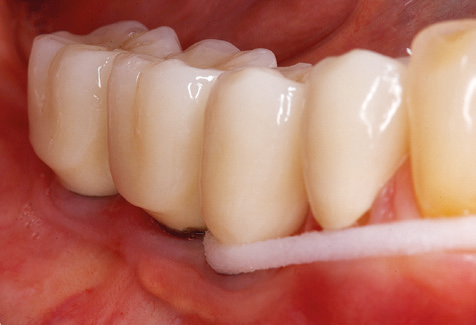

Fig. 4: Flexible probes with millimetre markings are recommended for the probing of dental implants (e.g. Colorvue Kit PCV11KIT6, Hu­Friedy). – Fig. 5a and b: A straight working tip (1P, W&H Dentalwerk Bürmoos GmbH) is a suitable instrument for use on all natural teeth. – Fig. 6: Curved working tips (3Pr/3Pl, W&H Dentalwerk Bürmoos GmbH) lend themselves to the processing of difficult-to-reach areas of the tooth and root surfaces (e.g. furcations). – Fig. 7: The tapered, hexagonal implant cleaning tip (1I, W&H Dentalwerk Bürmoos GmbH) permits atraumatic and efficient cleaning of the crown and abutment surfaces. – Fig. 8: Titanium and carbon curettes are suitable instruments for the manual cleaning of the implant surfaces.

Good illumination of the working field facilitates the process considerably. The system used by the authors achieves this thanks to a 5x LED ring integrated in the handpiece. Naturally, a range of working tips for different indications is also offered. A straight, universally employable tip is the basic instrument required for machine cleaning of natural teeth (Fig. 5a and b). Curved tips, which allow access to exposed furcations, are also available for hard-to-reach areas in the posterior region (Fig. 6).

Fig. 9: The accessible implant and tooth surfaces are polished with polishing cups and suitable polishing compounds. – Fig. 10: Repeat instruction in the use of appropriate aids for oral hygiene at home should also form part of SPT. – Fig. 11a and b: Clinical situation 12 years after insertion of the prosthetic restoration. During this period, only a veneering ceramic fracture on tooth 47 and the requirement for endodontic treatment of tooth 12 were observed. All restorations are still functioning as intended.

Standardised and regular risk-adapted care in the scope of SPT is the key to treatment success for the clinical long-term success in periodontically compromised patients. This is particularly true for patients fitted with implants following successfully completed periodontal treatment (Fig. 11a and b).